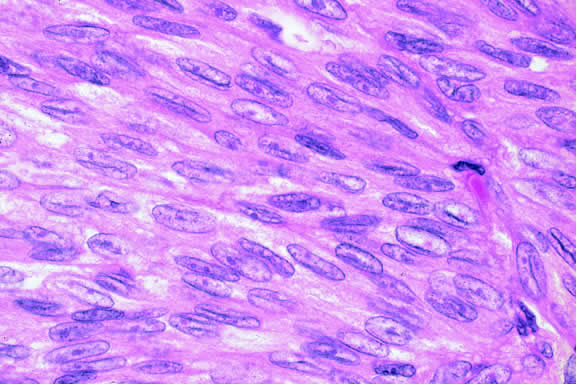

Nevi constitute the benign end of the biologic spectrum of melanocytic neoplasms. Most nevi are bland spindle cells tumors. Histopathologically, the choroidal stroma typically is replaced by a compact infiltrate of slender pigmented or nonpigmented spindle cells (Fig. 2). The nevus cells have bland oval or cigar-shaped nuclei that have finely dispersed chromatin and lack nucleoli or nuclear folds. Intranuclear cytoplasmic inclusions are common in some cases. Mitotic activity is absent. In some cases, the nevus cells are plump and dendritic in shape.9 Foamy balloon cells that appear to be undergoing lipoidal degeneration are found in 4% of nevi.4 Maximally pigmented, plump, polyhedral nevus cells comprise the magnocellular variant of nevus called melanocytoma (see later).

Fig. 2. Choroidal nevus. Choroidal stroma contains an infiltrate of pigmented spindle cells with bland nuclei. The retinal pigment epithelium is intact and the overlying retina remains attached. (Hematoxylin-eosin, × 100.)